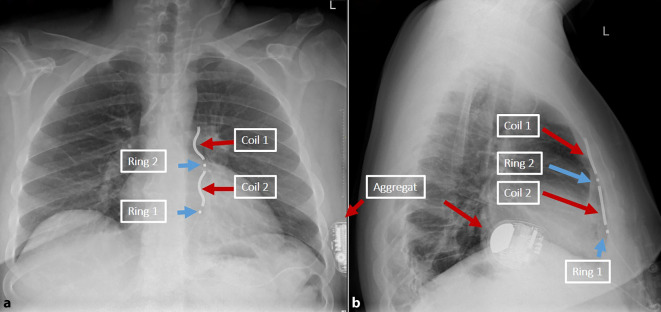

As an alternative to transvenous ICD systems, two non-transvenous ICD systems have been established in recent years: The subcutaneous ICD (S-ICD), which has been established for several years, has a presternal electrode that is implanted subcutaneously and offers a shock function and, to a limited extent, post-shock pacing. In addition, the extravascular ICD (EV-ICD) has been available in Europe since 2023 which does not require transvenous electrodes and offers the option of providing patients with antibradycardic and antitachycardic stimulation in combination with a conventional ICD function. The lead of this device is implanted substernally. Initial implantation results are promising in terms of safety and effectiveness. Both systems avoid possible complications of transvenous electrodes. This article provides practical guidance for the implantation technique and possible complications.

作为经静脉 ICD 系统的替代方案,近年来出现了两种非经静脉 ICD 系统:皮下 ICD(S-ICD)已问世数年,其胸骨前电极植入皮下,具有电击功能,并在一定程度上提供电击后起搏。此外,血管外 ICD(EV-ICD)已于 2023 年在欧洲上市,它不需要经静脉电极,可为患者提供抗心动过缓和抗心动过速刺激以及传统的 ICD 功能。该设备的导联是在体下植入的。就安全性和有效性而言,初步植入结果令人满意。这两种系统都避免了经静脉电极可能出现的并发症。本文就植入技术和可能出现的并发症提供实用指导。